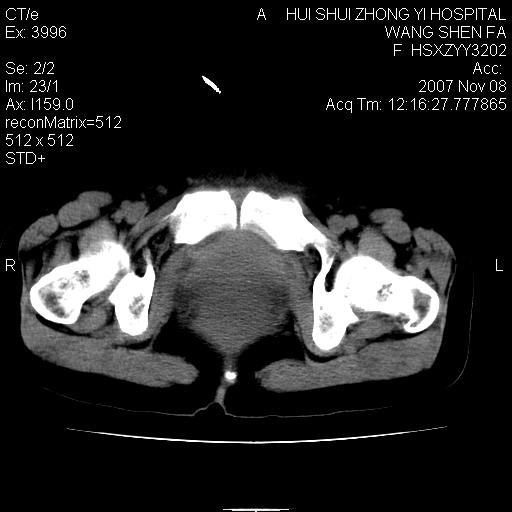

标题: CT10389:女,38岁,腹部巨大包块 [打印本页]

标题: CT10389:女,38岁,腹部巨大包块

腹部巨大包块半年,质硬,边界不清。

盆腔及下腹部多发肿块,密度不均,与子宫关系密切,周围肠管受压改变,盆腔内未见肿大淋巴结,考虑多发性巨大子宫肌瘤可能。直接手术吧!

下腹部巨大软组织影,密度不均匀,并可见分隔,病灶边缘较清,肠管受压移位。病灶下部与子宫及附件关系密切。盆腔、双侧腹股沟未见明显肿大淋巴结。考虑:1.卵巢实质性肿瘤可能性大,卵巢癌>颗粒细胞>卵泡膜细胞瘤>纤维瘤.2.多发子宫肌瘤待除外.

下腹部巨大软组织影,密度不均匀,并可见分隔,病灶边缘较清,肠管受压移位。病灶下部与子宫及附件关系密切。盆腔、双侧腹股沟未见明显肿大淋巴结。考虑:1.卵巢实质性肿瘤可能性大,卵巢癌>颗粒细胞>卵泡膜细胞瘤>纤维瘤.2.多发子宫肌瘤待除外.3)间叶组织来源(脂肪肉瘤、平滑肌肉瘤)。

膀胱向前明显的推压移位,子宫增大明显,肠管推压移位,未见明显的侵润;患者女性,育龄期,考虑多发子宫肌瘤可能性大